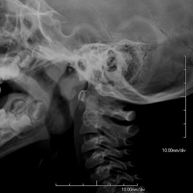

- RX Columna cervical

Tècnica que usa els raigs X a través de la qual s'obtenen imatges de la columna cervical per al seu estudi. Indicacions: traumatisme, contractura cervical, dolor articular. - RX Ossos propis nasals

Tècnica que usa els raigs X a través de la qual s'obtenen imatges de la columna cervical per al seu estudi. Indicacions: traumatisme, dolor cervical. - RX Columna dorsal